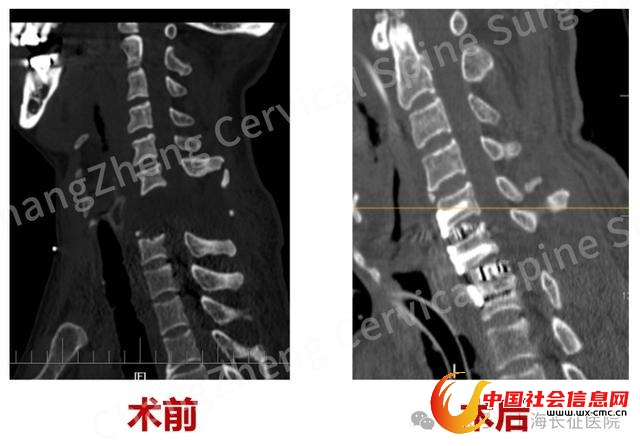

该院骨科副主任、颈椎外科病区主任陈华江介绍,这例大跨度颈椎脱位病例极为凶险。患者李某因颈部遭受机械臂重击,导致颈椎瞬间遭受毁灭性损伤,当场高位截瘫、心跳骤停,经紧急心肺复苏才勉强恢复微弱生命体征。影像学检查显示,其颈椎发生了罕见的大跨度脱位,严重程度犹如“身首离断”,造成脊髓严重挫伤、关键神经血管结构撕裂。

手术台上,在患者极其脆弱的生命体征监护下,专家们凭借精湛的解剖功底和显微操作技术,小心翼翼地清除巨大血肿,克服严重粘连和畸形,最终精准地将完全离断错位的颈椎结构复位。尤为关键的是,团队创新性地应用了“卫星钢板”固定技术,在常规固定之外巧妙增加辅助钢板,为重建的颈椎提供了前所未有的超强稳定性,这一技术应用在此类极端病例中尚属首创。